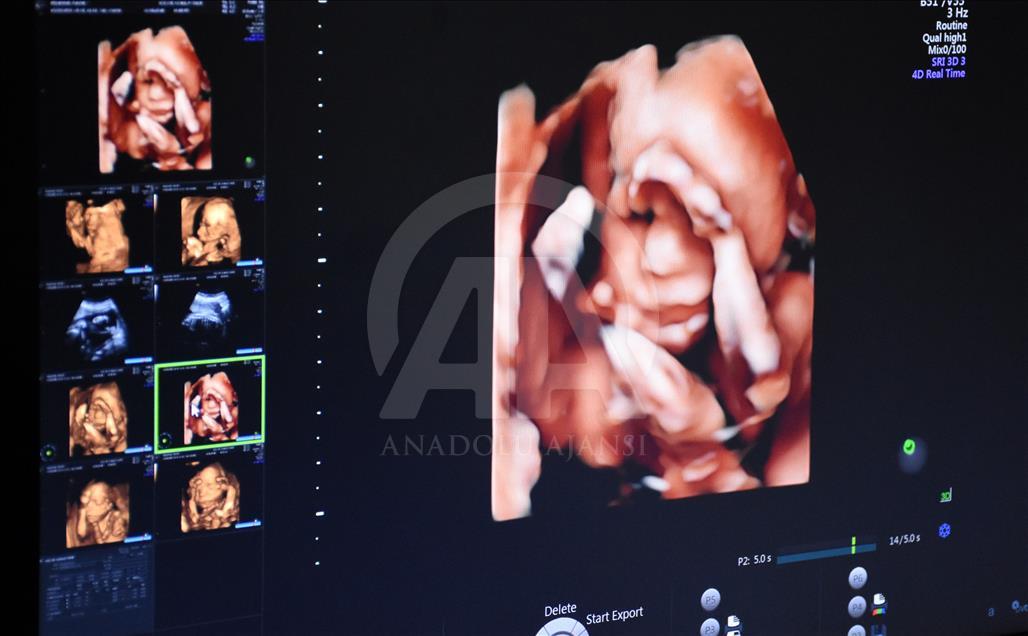

Anne karnındaki bebeklerin ilginç ultrason görüntülerini yakalayan ve bu görüntülerden özel bir köşe oluşturan kadın hastalıkları ve doğum uzmanı Doç. Dr. Gökalp Öner'in, yaklaşık 4 bin fotoğraflık koleksiyonu bulunuyor. Doç. Dr. Öner, AA muhabirine yaptığı açıklamada, sadece bir koleksiyon sahibi olmanın değil, anne ve babalara güzel bir hatıra oluşturmanın mutluluğunu da yaşadığını belirterek, "Doğumdan sonra aileler bizi ziyarete geldiği zaman kendi köşeleri olsun ve orada fotoğraf çektirelim istedik. Böylece, yaklaşık 4 bin ultrason fotoğrafına ulaştık." dedi. ( Müzahim Zahid Tüzün - Anadolu Ajansı )